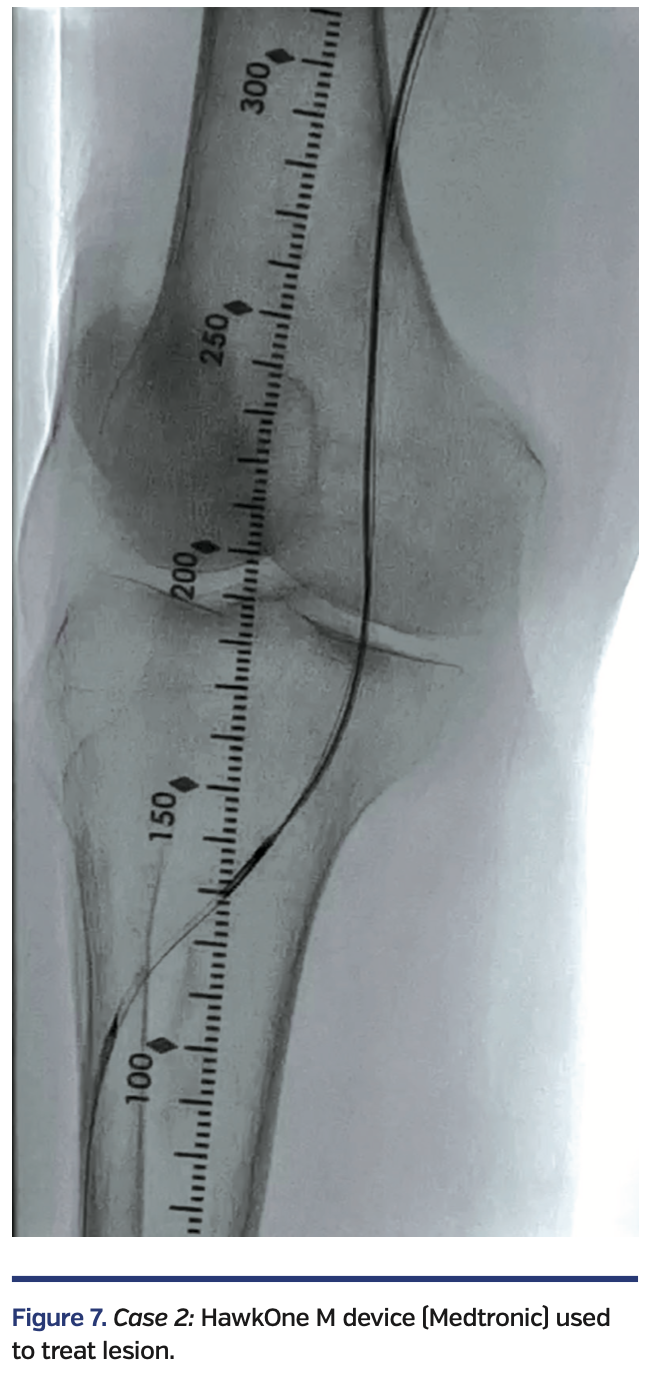

The Enteer wire was exchanged out for a V-18 wire that was subsequently externalized via the right common femoral artery sheath. Over an antegrade Fielder FC wire, intravascular ultrasound (IVUS) evaluation was performed with an .014-inch IVUS catheter, followed by directional atherectomy with a HawkOne M device (Medtronic) (Figure 7).

Sequential balloon angioplasty in the anterior tibial artery was performed with 2.0 mm and 4.0 mm Coyote balloon (Boston Scientific). Kissing balloon angioplasty of the popliteal artery, proximal anterior tibial, and tibioperoneal trunks was performed with long 3 mm balloons, followed by drug-coated balloon angioplasty of the right femoropopliteal segment with a 6 mm x 250 mm IN.PACT Admiral drug-coated balloon (Medtronic). There was restoration of normal flow in all treated segments (Figure 8), with a warm foot and a palpable dorsalis pedis artery at the end of the case.